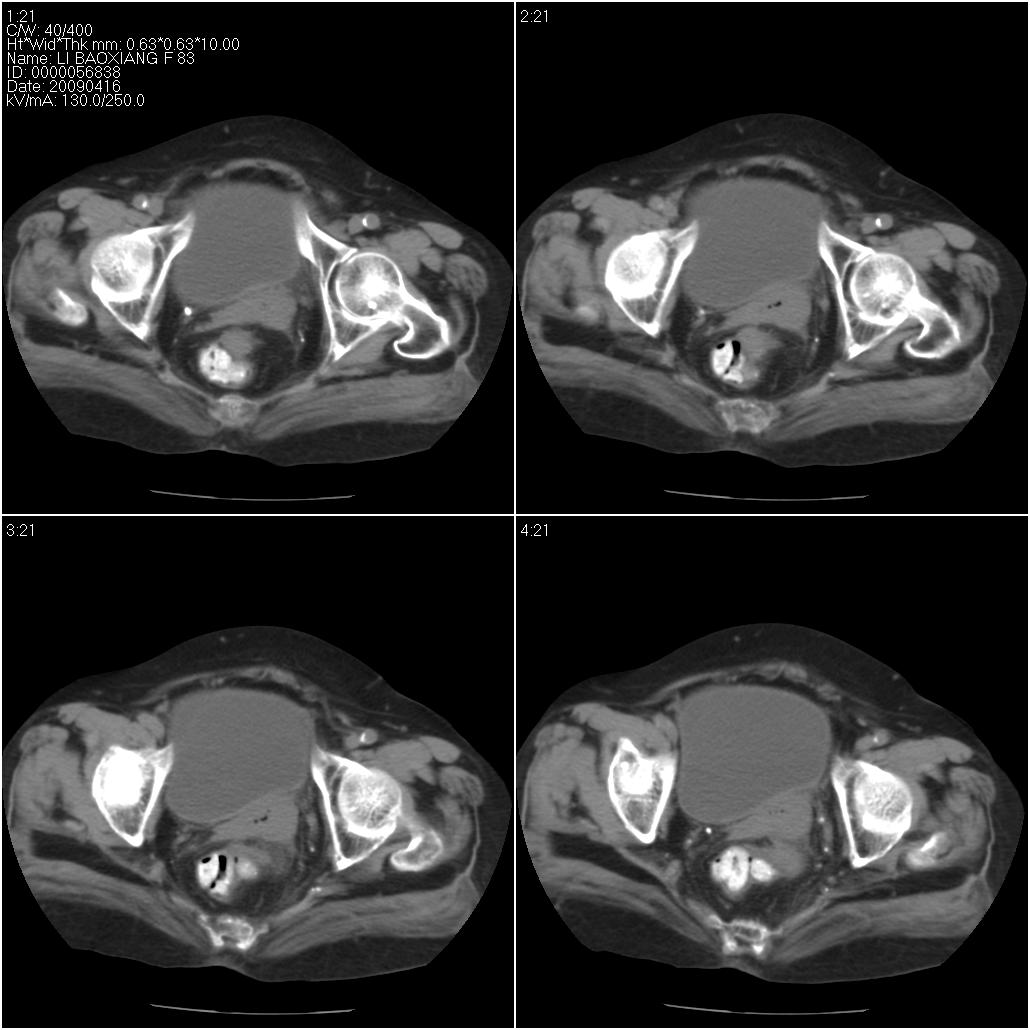

标题: CT19496:女性,83岁。阴道出血多年,患者一般情况良好。 [打印本页]

标题: CT19496:女性,83岁。阴道出血多年,患者一般情况良好。

乙状结肠病变累及子宫,建议结合妇科检查

考虑乙状结肠肿瘤累及子宫;建议行肠镜检查。

考虑:乙状结肠癌累及子宫,建议钡剂灌肠。

乙状结肠癌累及子宫

乙状结肠癌侵犯子宫可能性大。